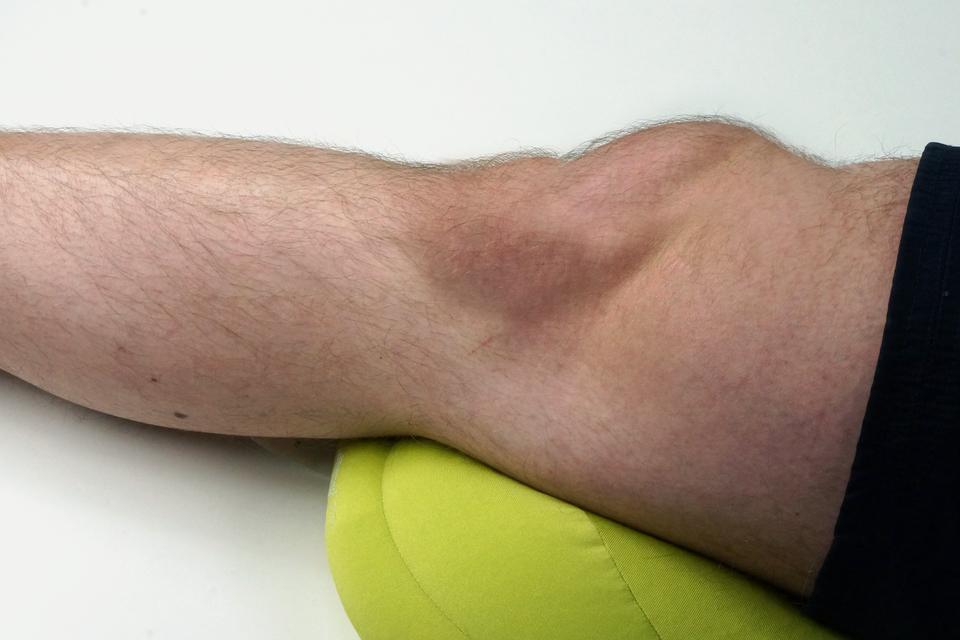

Do najczęstszych urazów mechanicznych układu ruchu należą złamania, zwichnięcia i skręcenia, które różnią się mechanizmem powstania i zakresem uszkodzeń.

Zwichnięcia stawu polegają na przemieszczeniu się powierzchni stawowych względem siebie. Może im towarzyszyć naciągnięcie lub rozerwanie torebki stawowej. Korekcję zwichniętego stawu przeprowadza lekarz oceniając jednocześnie czy nie doszło do uszkodzenia nerwów i naczyń krwionośnych.

Skręcenia stawu to uszkodzenie torebki stawowej bez przemieszczenia kości w jego obrębie. Nawet pozornie lekkie skręcpowinny być ocenione przez lekarza, aby wykluczyć zerwanie więzadeł lub poważniejsze uszkodzenia stawu.